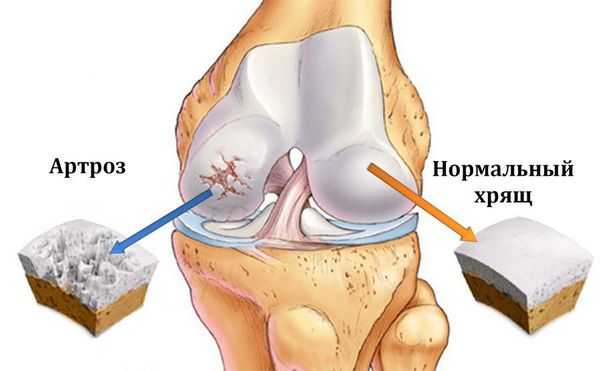

Первое существенное изменение при остеоартрозе – смягчение и образование ямок на гладкой поверхности хряща. По мере прогрессирования артрита слой хряща, покрывающий суставные поверхности, становится все тоньше, вплоть до полного разрушения, оставляя незащищенными концы костей.

Без нормальной скользящей поверхности становится болезненным и трудным двигать суставом. Поскольку хрящ продолжает разрушаться, по краям сустава формируются костные выросты, как бы компенсирующие потерю хряща за счет увеличения суставных поверхностей. Это является причиной деформаций суставов (сустав теряет свою форму) при артрите. В народе подобное состояние называют "отложение солей", что является просто неграмотным названием артроза.

Патогенез остеоартроза

Основной питательной средой сустава является синовиальная жидкость. Она же выполняет и роль смазывающего агента между суставными поверхностями. Огромную и главную роль в развитии остеоартроза отводят метаболическим процессам в суставе и в его структурах. На начальной стадии, когда развиваются биохимические нарушения в синовиальной жидкости, ее свойства снижаются, что запускает механизм разрушения. Первой под удар попадает синовиальная оболочка сустава, которая выполняет важную роль мембраны и является подобием фильтра для самого главного питательного вещества хряща — гиалуроновой кислоты, не давая ей покинуть ее основное место работы — полость сустава. Насыщенность свойств суставной жидкости определяет ее циркуляция, чего без регулярного движения самого сустава быть не может. Отсюда и известная фраза «движение — это жизнь». Постоянная циркуляция синовиальной жидкости в полости сустава — залог полноценного обмена веществ в нем. При недостатке питательных веществ хрящ истончается, образование новых клеток останавливается, суставная поверхность становится неровной, грубой, с участками дефектов. Известна взаимосвязь между заболеваниями вен нижних конечностей (например, варикоз) и развитием нарушений обмена веществ в суставах, преимущественно коленных. [6] Костная структура, находящаяся под хрящевой, отвечает на процесс компенсаторным механизмом — она утолщается, становится грубее и расширяет зону покрытия, в результате чего образуются экзостозы и остеофиты, что и является основной причиной ограничений и деформаций сустава. Синовиальная жидкость насыщается клетками воспаления и элементами распада, суставная капсула в ответ на это утолщается, становится грубой и теряет эластичность, мягкие ткани буквально становятся сухими (происходит их дегидратация), отсюда и жалобы на утреннюю скованность, «стартовые боли». Патологический процесс в последних стадиях провоцирует организм включить последний компенсаторный механизм — обездвиживание. В состоянии покоя и так называемом физиологическом положении болезненность минимальна, связочный аппарат максимально расправлен. В таком положении сустав стремится зафиксироваться, и ему это удается быстрым образованием более грубых экзостозов, которые «фиксируют» сустав, а пациент при этом теряет способность полноценно двигать им. Мышцы такой конечности гипотрофируются, становятся слабее и меньше. Такие изменения уже считаются необратимыми.